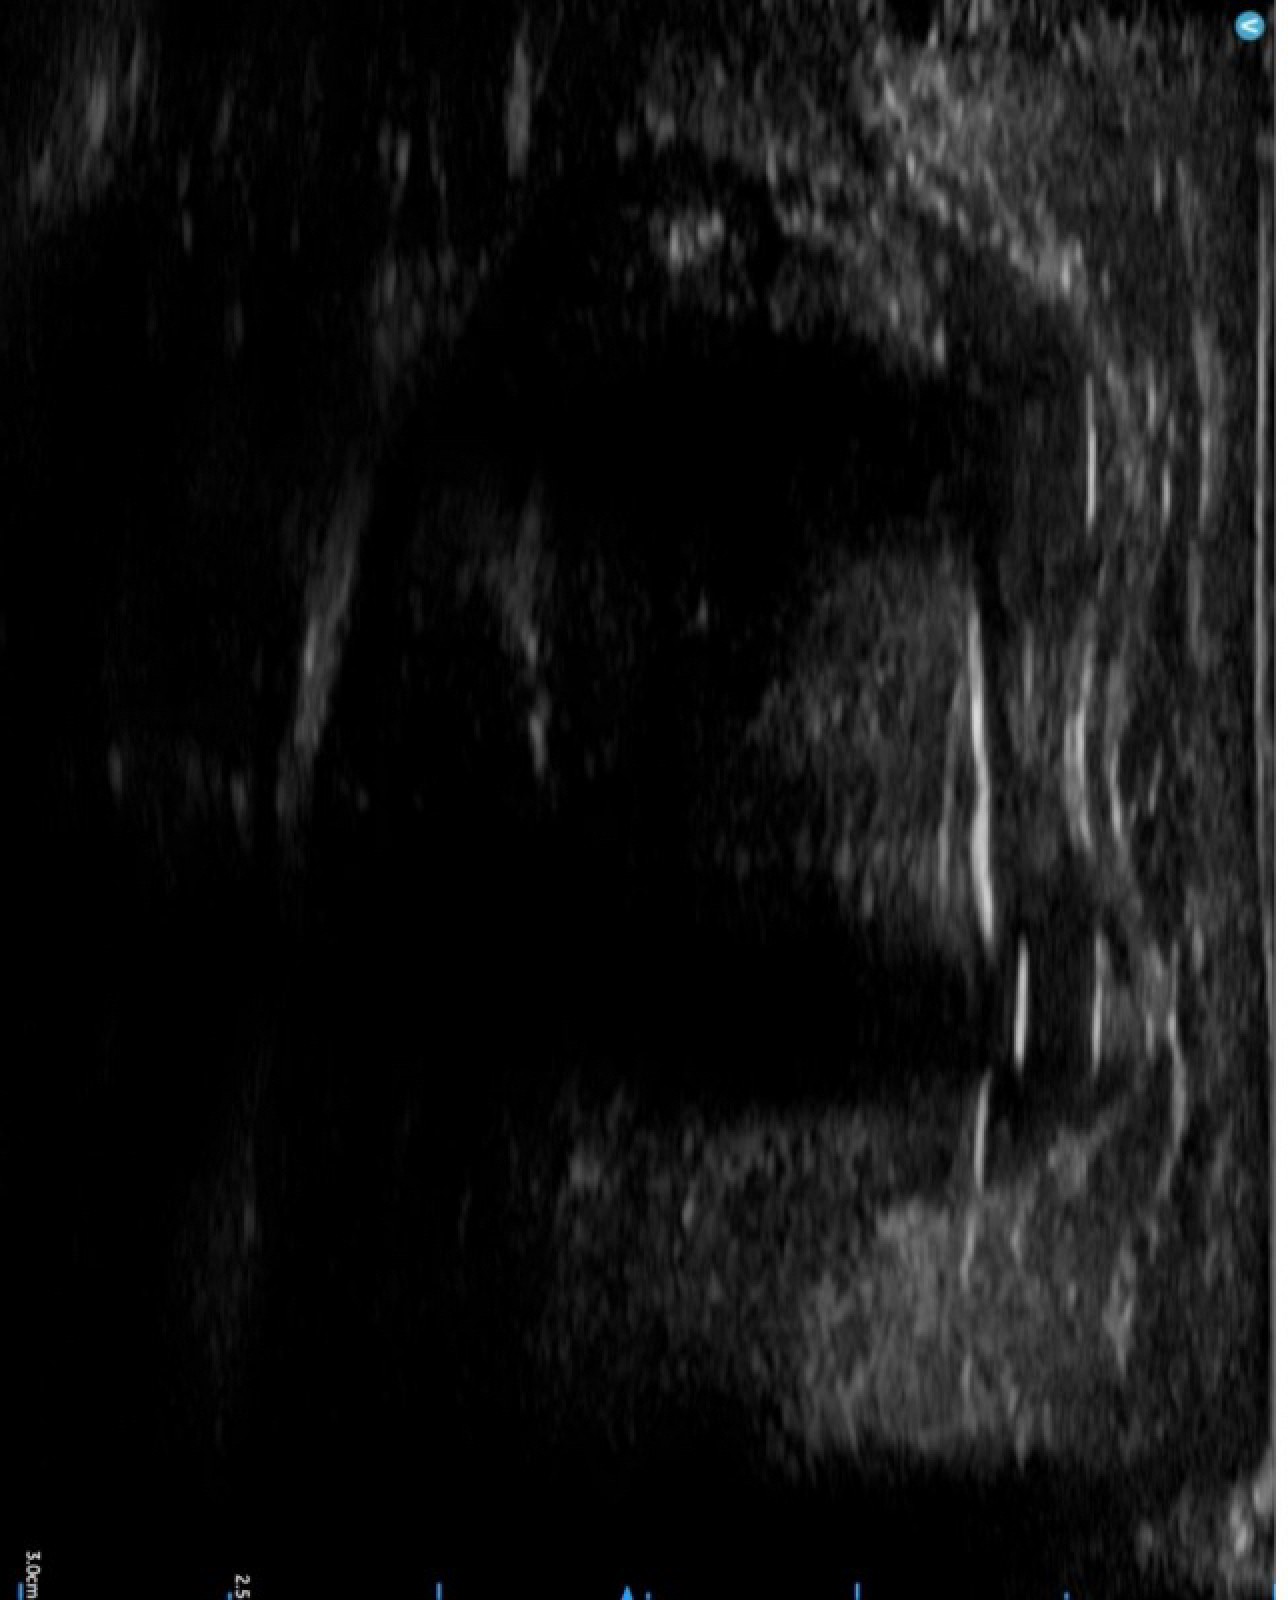

Par une ouverture cutanée de 2 cm, on insert l’Achillon qui est une sorte de fourchette à 4 branches trouées. Les 2 branches externes restent dehors et les 2 internes sont au contact du tendon. Les fils sont passés dans les trous des branches. On peut suivre l’avancée des fils et vérifier le passage dans l’épaisseur du tendon grâce à un contrôle échographique. On retire la fourchette, il ne reste alors que les fils dans le tendon qui sortent au niveau de l’incision. On noue les fils en redonnant une bonne longueur au tendon.